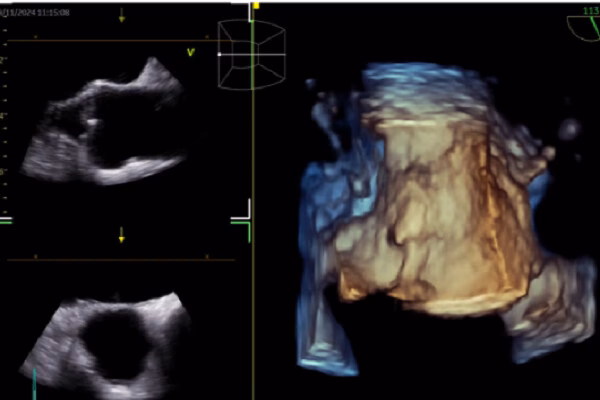

Theo bác sĩ Nhật, hình ảnh học tim mạch là lĩnh vực có nhiều nghiên cứu và ứng dụng AI nhất. Các công nghệ như điện tâm đồ (ECG), siêu âm tim, CT tim, MRI tim, đặc điểm lâm sàng, tiên lượng và quyết định lâm sàng đang được tích hợp AI để nâng cao hiệu quả chẩn đoán và điều trị. AI đã được ứng dụng trong ECG để dự đoán rung nhĩ, suy tim có phân suất tống máu giảm và hẹp van động mạch chủ. Trong siêu âm tim, AI giúp nhận diện cấu trúc cơ tim, đo đạc tự động và hỗ trợ báo cáo và chẩn đoán.